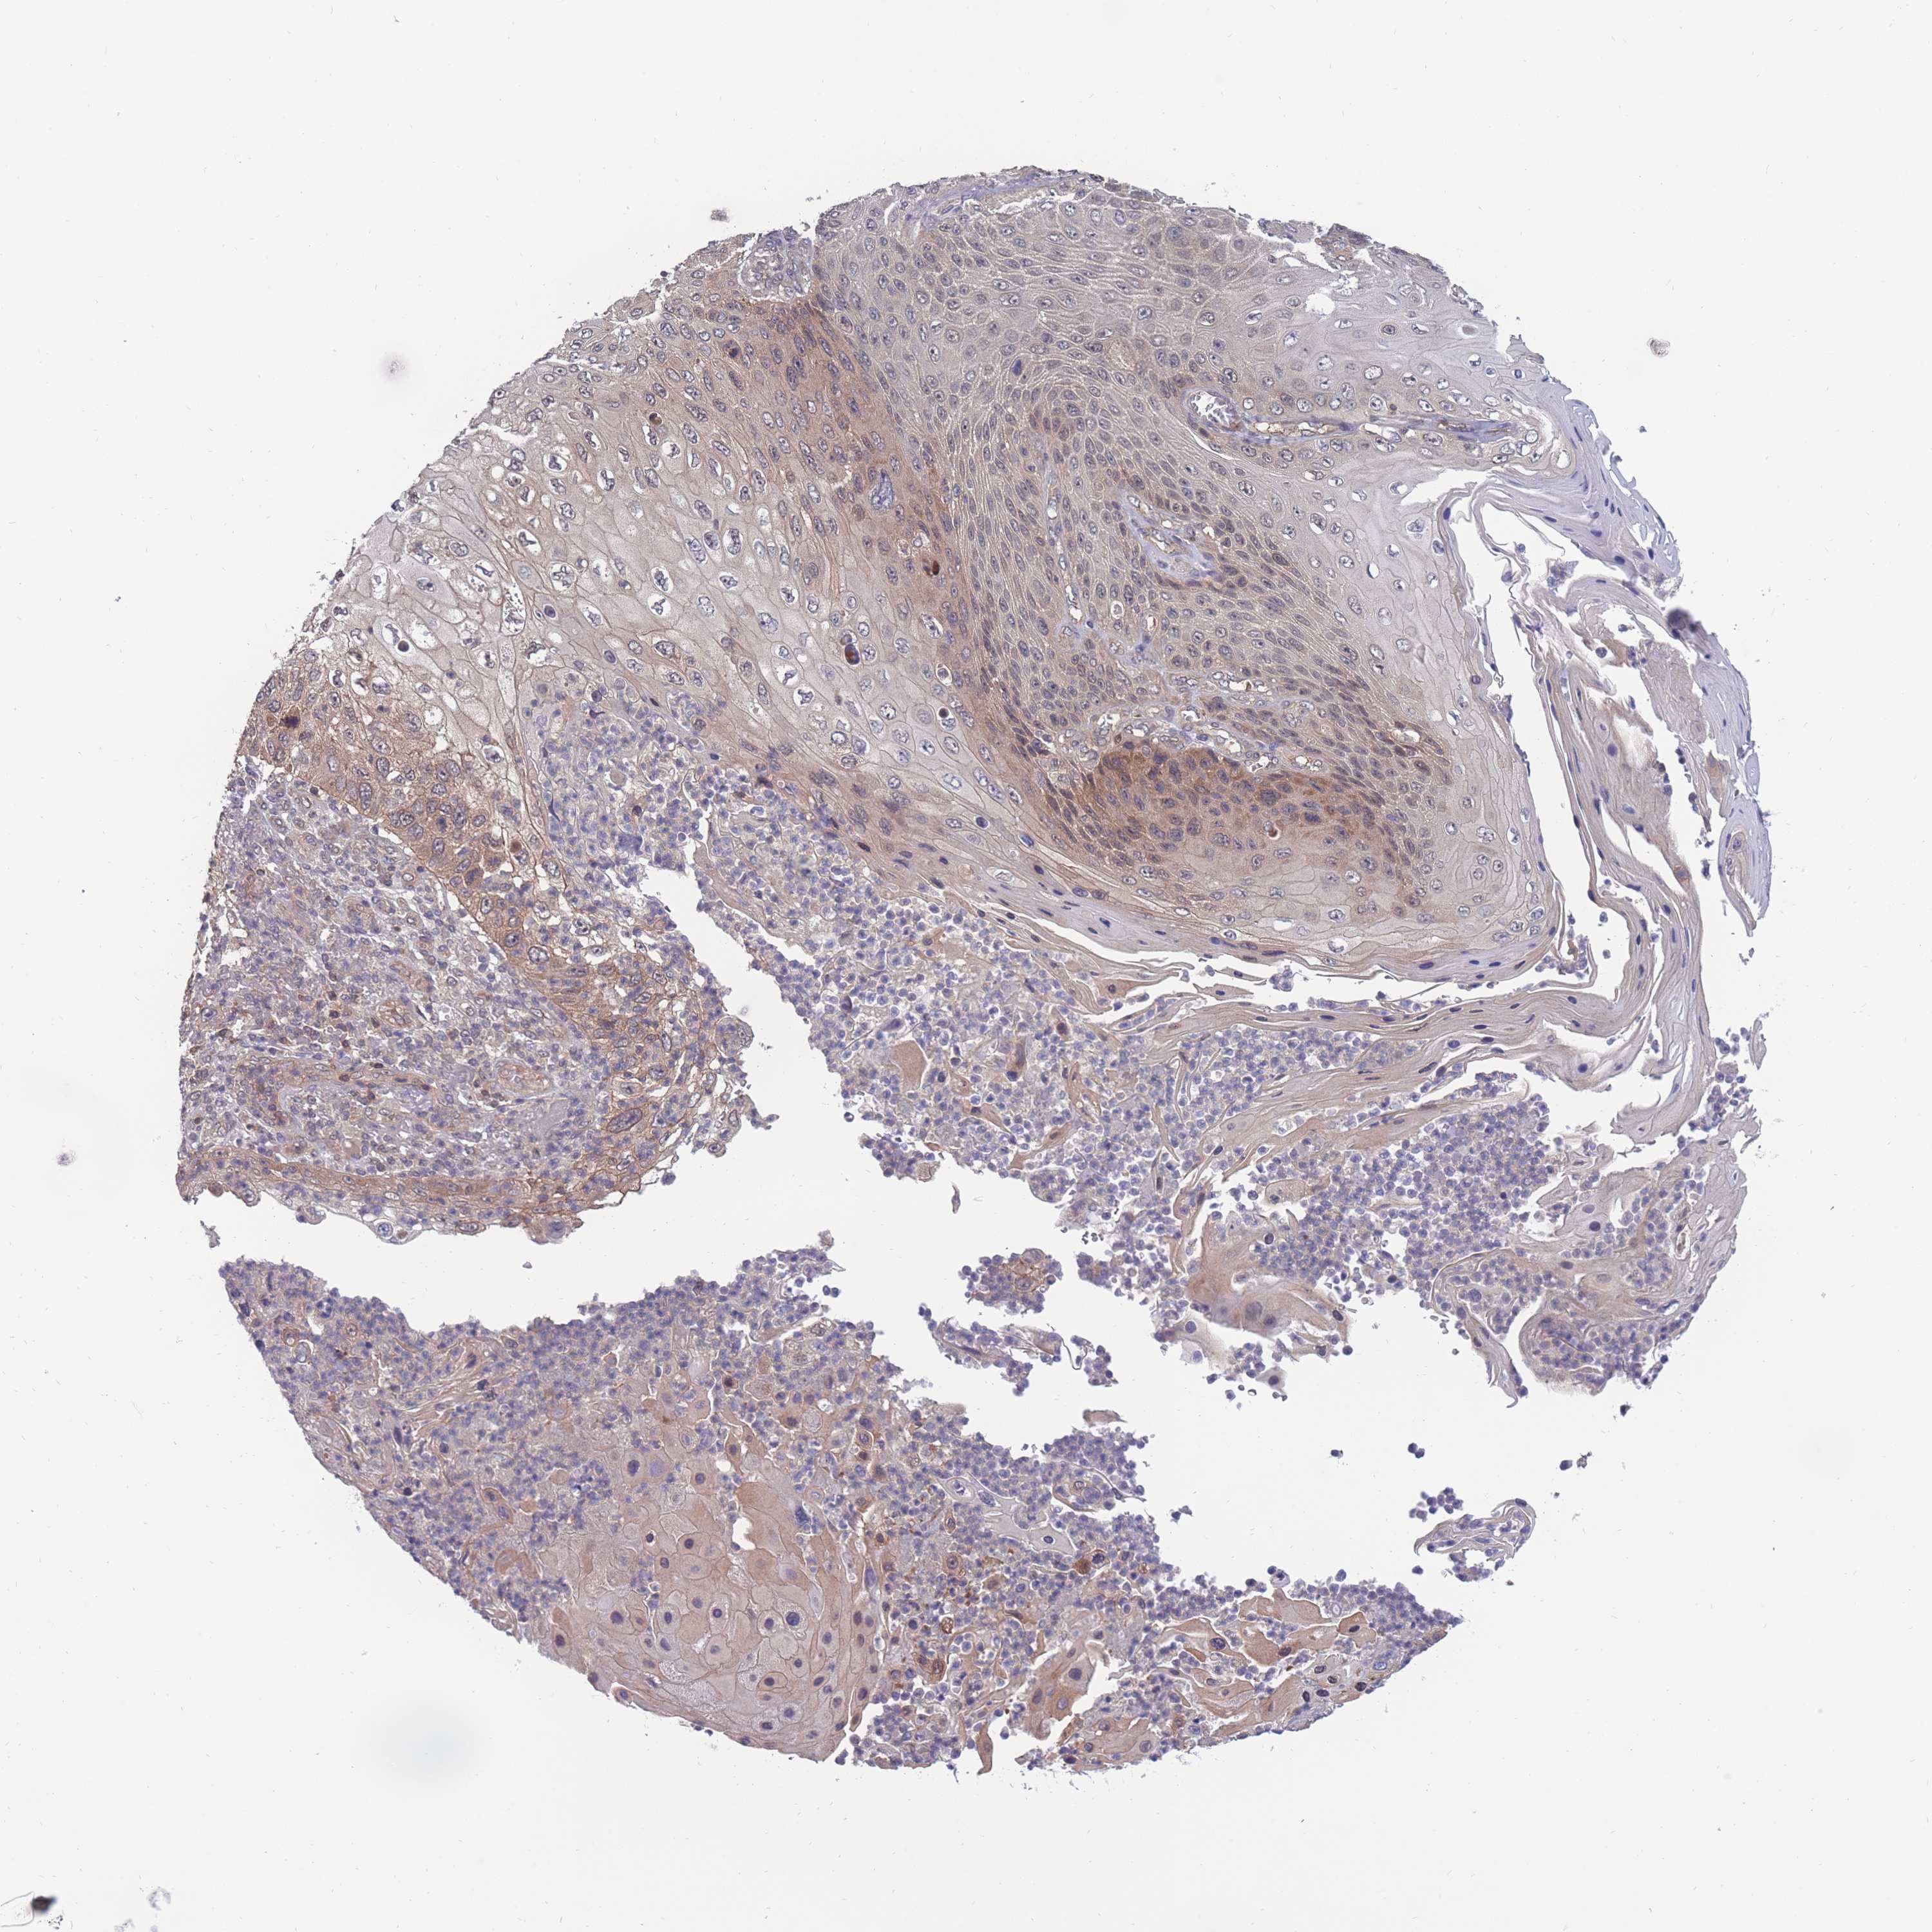

CANCER SKIN CANCER Show tissue menu

Basal cell and squamous cell cancer

SKIN CANCER - Protein expressioni

A mouse-over function shows sample information and annotation data. Click on an image to view it in a full screen mode. Samples can be filtered based on level of antibody staining by selecting one or several of the following categories: high, medium, low and not detected. The assay and annotation is described here.

Each image is clickable and will lead to virtual microscopy that enables deeper exploration of all samples and also displays staining intensity scores, fraction scores and subcellular localization as well as patient and tissue information for each sample.

Antibody HPA044976

Staining

High

Medium

Low

Not detected

Intensity

Strong

Moderate

Weak

Negative

Quantity

>75%

75%-25%

<25%

None

Location

Nuclear

Cytoplasmic/membranous

Cytoplasmic/membranous,nuclear

Basal cell carcinoma

Squamous cell carcinoma, NOS

Squamous cell carcinoma, metastatic, NOS